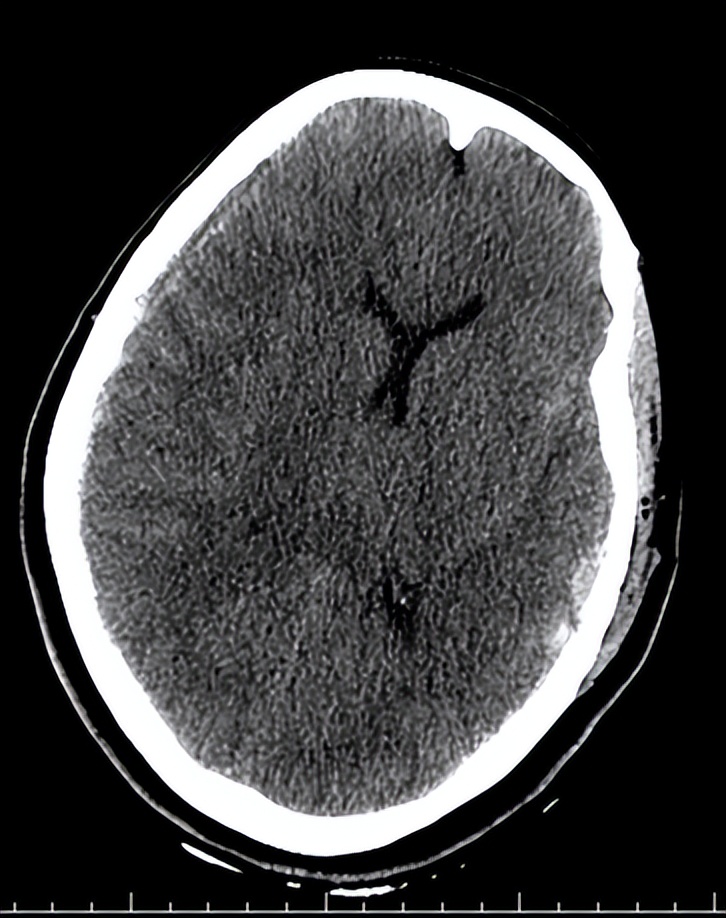

06-07 21:30术后复查头CT示:

06-08术后第一天复查头CT示: